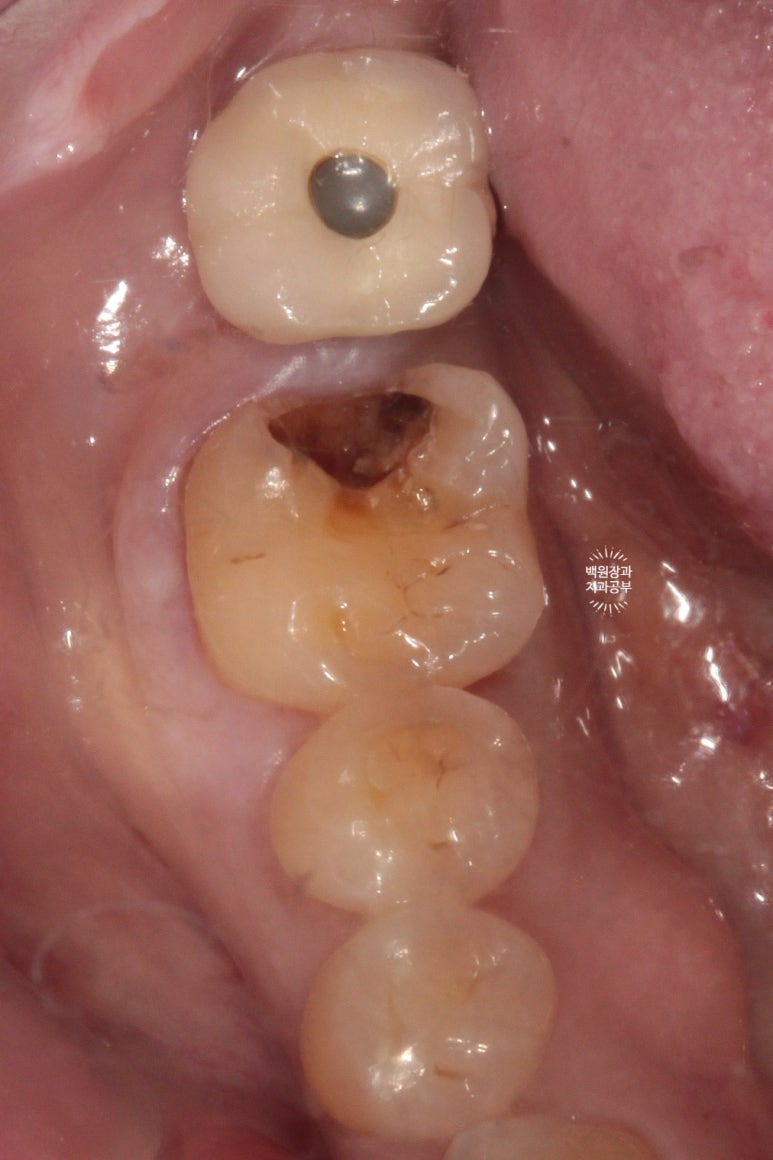

자, 2차 충치를 제거해 보겠습니다.

충치가 깊으면 신경치료를 해야할 수도 있다고 설명해드렸어요.

기존의 골드 인레이를 제거하였을 때, 하방에 존재했던 광범위한 2차 우식을 관찰할 수 있었어요.

제거를 시작해 보겠습니다.

어디까지 제거하냐면, 단단한 치질 (상아질)이 확보될 때 까지입니다.

(꼭 하얀색이 아닐 수 있어요. 보통 약간 누리끼리 합니다.)

처음에는 high speed angle을 이용하여 경계부를 제거해 줍니다.

이 후 치아 내부의 신경관 노출을 최소화 하기 위해서 마무리는 손기구 (hand instrument)로 진행!

결과적으로 2차 우식을 조심히 제거하여 치아 내부의 신경 노출을 피할 수 있었습니다.!!!